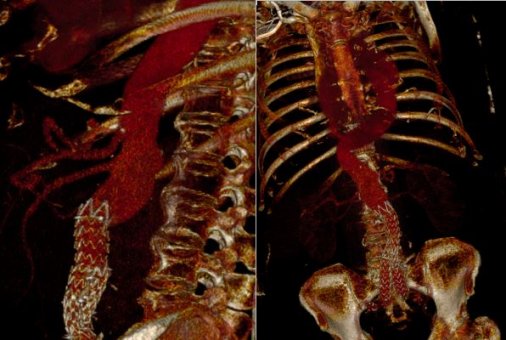

Ο 71χρονος ασθενής είχε υποβληθεί στο παρελθόν σε ενδαγγειακή αποκατάσταση ανευρύσματος κοιλιακής αορτής σε νοσοκομείο της βόρειας Ελλάδας με το μόσχευμα να έχει μετατοπιστεί και υπήρχε σημαντικός κίνδυνος ρήξης του θωρακοκοιλιακού ανευρύσματος διαμέτρου 8 εκατοστών.

Σχεδιάστηκε ειδικό κατά παραγγελία μόσχευμα για το συγκεκριμένο ασθενή (custom made fenestrated stent graft) και η ελάχιστα επεμβατική αντιμετώπιση (από 3 μικροσκοπικές τομές), υπό ακτινοσκόπηση πραγματοποιήθηκε με τη συνεργασία του ειδικού τμήματος για τις συγκεκριμένες παθήσεις που λειτουργεί στο Mediterraneo.

Η θυριδωτή μέθοδος εφαρμόζεται εδώ και δύο χρόνια στο Mediterraneo Hospital και αποτελεί ελάχιστα επεμβατική μέθοδο αντιμετώπισης των θωρακοκοιλιακών και παρανεφρικών ανευρυσμάτων της αορτής με χαμηλότερη νοσηρότητα και πολύ καλύτερα αποτελέσματα σε σύγκριση με την ανοικτή μέθοδο αποκατάστασης των δύσκολων αυτών ανευρυσμάτων.